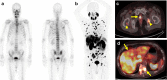

Results: We reviewed 57 original research articles during the period 2016-2021: 14 articles regarding the radiotracer PSMA; 18 articles regarding the primary tumor detection, local tumor staging, managing local recurrence; 17 articles for managing lymph node metastases; and eight articles for managing bone and other distant metastases. PSMA PET could be complementary to mpMRI for primary prostate cancer localization and is particularly valuable for PI-RADS three lesions. PET-MRI is better than PET-CT in local tumor staging due to its specific benefit in predicting extracapsular extension in MRI-occult prostate cancer patients. PET-MRI is likely superior as compared with PET-CT in detecting local recurrence, and has slightly higher detection rates than PET-CT in lymph node recurrence. PET-CT and PET-MRI seem to have equivalent performance in detecting distant bony or visceral metastases.

Conclusion: In conclusion, PET-MRI is suitable for local and regional disease, either primary staging or restaging, whereas PET-CT is valuable for managing distant bony or visceral metastasis.